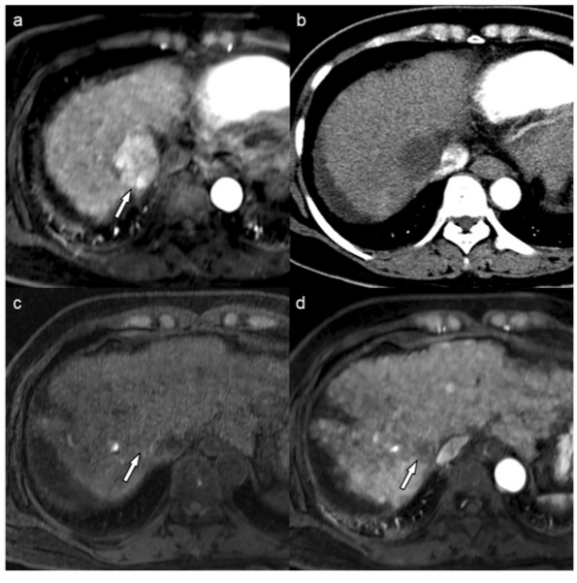

圖 50歲女性肝細(xì)胞癌(HCC)的MR和CT圖像。動(dòng)脈期MR圖像顯示肝臟第7段有一個(gè)4.2厘米的HCC(箭頭)(a)。經(jīng)過(guò)一個(gè)療程的藥物洗脫珠-TACE治療后,患者獲得了持久的影像學(xué)完全反應(yīng)(b)。肝移植時(shí),對(duì)比前(c)和動(dòng)脈期(d)的MR圖像將目標(biāo)病變分配為LR-TR非生存類別(箭頭)。術(shù)前血清AFP水平為3.3納克/毫升。風(fēng)險(xiǎn)評(píng)分為0,患者屬于有利的風(fēng)險(xiǎn)組。手術(shù)后,證實(shí)了病理上可行的腫瘤,60%的腫瘤已經(jīng)壞死。患者在術(shù)后104.6個(gè)月內(nèi)一直存活且無(wú)復(fù)發(fā)